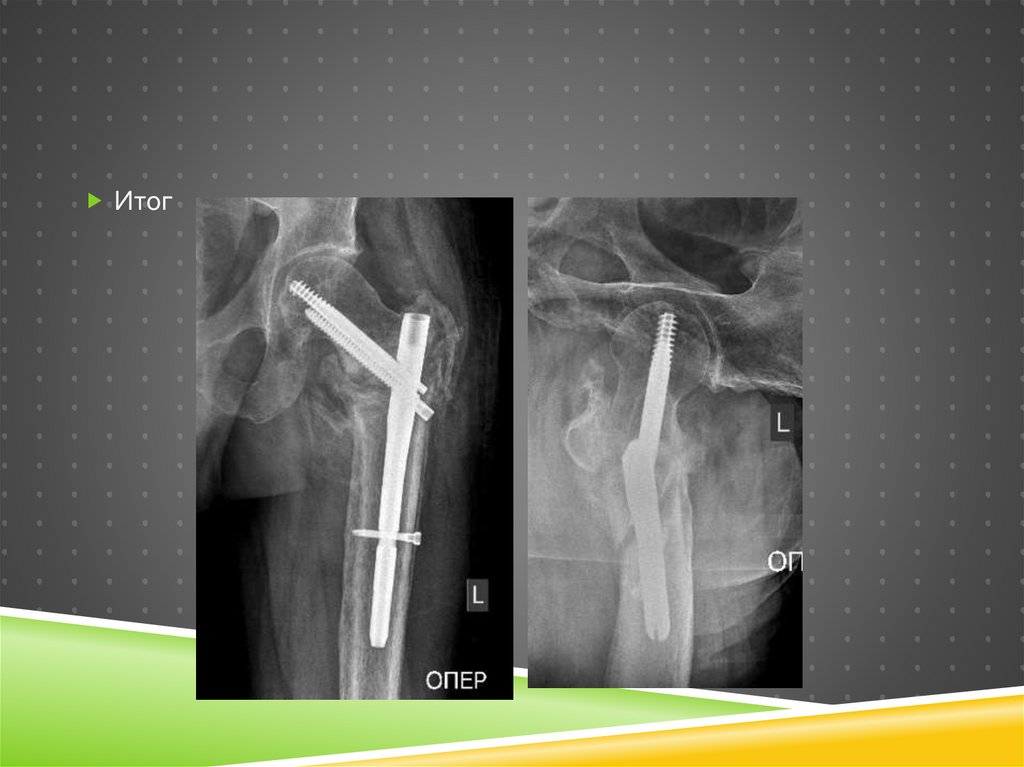

Итог

98.